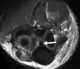

Intraarticular loose body